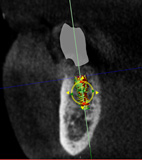

A healthy 60-year-old female presented for an emergency evaluation because she was experiencing pain associated with tooth No. 20. It was mobile, malposed, and given a diagnosis of irreversible pulpitis. In addition, teeth Nos. 19 and 21 had been missing for more than 5 years. After the evaluation, a discussion revealed that the patient desired implant reconstruction of the lower left quadrant. During this initial visit, a CBCT scan was obtained, and the virtual restoration-driven implant planning was completed, confirming that extraction of tooth No. 20 with robot-assisted immediate implant placement at the sites of teeth Nos. 19 and 21 was a viable option (Figure 9 through Figure 13). Splint placement, CBCT capture of the fiducial array, calibration, and landmark confirmation were completed as described in the first case report. Following the administration of intravenous sedation and local anesthesia, tooth No. 20 was atraumatically extracted. Flap access was obtained from the site of tooth No. 18 to the site of tooth No. 22, and robot-assisted surgical implant placement was completed at the sites of teeth Nos. 19 and 21. Intraoperatively, guide pins were placed to evaluate the position of the proposed osteotomies, and it was determined that both implants should be tilted buccally by 0.4 mm. The necessary changes were made in the software application, and the new implant placement plan was immediately ready for robotic implementation. The implants were robotically delivered to their planned positions at the sites of teeth Nos. 19 and 21 and torqued to initial stability at 50 Ncm and 45 Ncm, respectively (Figure 14 and Figure 15). Healing abutments were placed, and the tissue was closed primarily. In this case, robotic assistance facilitated the performance of surgery on the same day that the patient initially presented and permitted intraoperative modifications to be made.

(12.) Postoperative CBCT image of actual implant placement at site No. 21.

Figure 12

(13.) Postoperative CBCT image of actual implant placement at site No. 19.

Figure 13